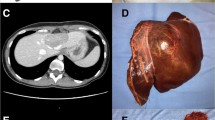

Robotic liver resections which were not performed minimally invasive before the introduction of robotic liver surgery in our center. a Robotic left hemihepatectomy with lymphadenectomy (Groups 1 and 2 lymph nodes: stations 7, 8, 9 and 12). Indication: large intrahepatic cholangiocarcinoma. b Robotic anatomical segment 3 resection—repeat hepatectomy after 3 open liver resections in a patient with large ventral hernia. Indication: colorectal liver metastasis. c Robotic-extended right hemihepatectomy with preservation of segment 4A, lymphadenectomy, wedge resection of stomach and hepaticojejunostomy (reimplantation bile duct of segment 4A and left lobe). Indication: gallbladder carcinoma invasion right hepatic artery, bile duct and invasion right anterior sectoral portal vein. d Left hemihepatectomy with resection of segment 1, extrahepatic bile duct, lymphadenectomy and hepaticojejunostomy (double barrel anastomosis). Indication: perihilar cholangiocarcinoma Bismuth–Corlette type IV

With the start of a robotic program in our institution, we noted a significant decrease in open liver procedures. We believe this is due to technically complex procedures that would have been performed in an open fashion in the laparoscopic era that can now be tackled by a robotic approach (Fig. 3). This view is supported by the observation that our robotic group consisted of more redo surgeries that had a significantly higher Southampton difficulty index. To illustrate this, our robotic group consisted of 9 patients undergoing a combined liver and bile duct resection with biliary reconstruction. No such resections were performed minimally invasive at our center before the introduction of robotic surgery. Previous studies have come to the same conclusion that robotic surgery allowed for a larger percentage of liver resections to be completed in a minimally invasive manner [21, 22]. This finding underlines the importance of robotic-assisted surgery in expanding patient selection for minimally invasive surgery.